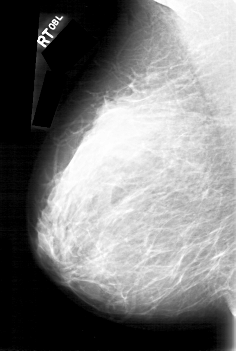

D_4092_1.RIGHT_CC

RIGHT_CC LINES 5341 PIXELS_PER_LINE 3466 BITS_PER_PIXEL 12 RESOLUTION 43.5 NON_OVERLAY